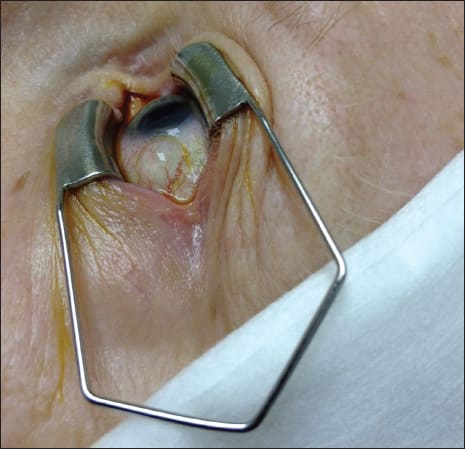

One must take into account the chemical properties of the aqueous vs vitreous humor when injecting intravitreal substances (bevacizumab, ranibizumab, aflibercept, antibiotics, steroids, etc.) into a previously vitrectomized eye. If prior surgery involved the removal of the vitreous base, one should expect a high incidence of leakage due to a lack of a vitreous plug to the injection site (Figure). The 23-gauge tunnel required for the injection of a dexamethasone intravitreal implant will have an even greater chance of leakage.

Figure. Subconjunctival bleb formation in a previously vitrectomized eye immediately following an injection of intravitreal bevacizumab.